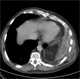

Old pleural empyema

A chest tube (chest drain, thoracic catheter, tube thoracostomy, or intercostal drain) is a flexible plastic tube that is inserted through the chest wall and into the pleural space or mediastinum. It is used to remove air (pneumothorax), fluid (pleural effusion, blood, chyle), or pus (empyema) from the intrathoracic space. [Source: Wikipedia ]